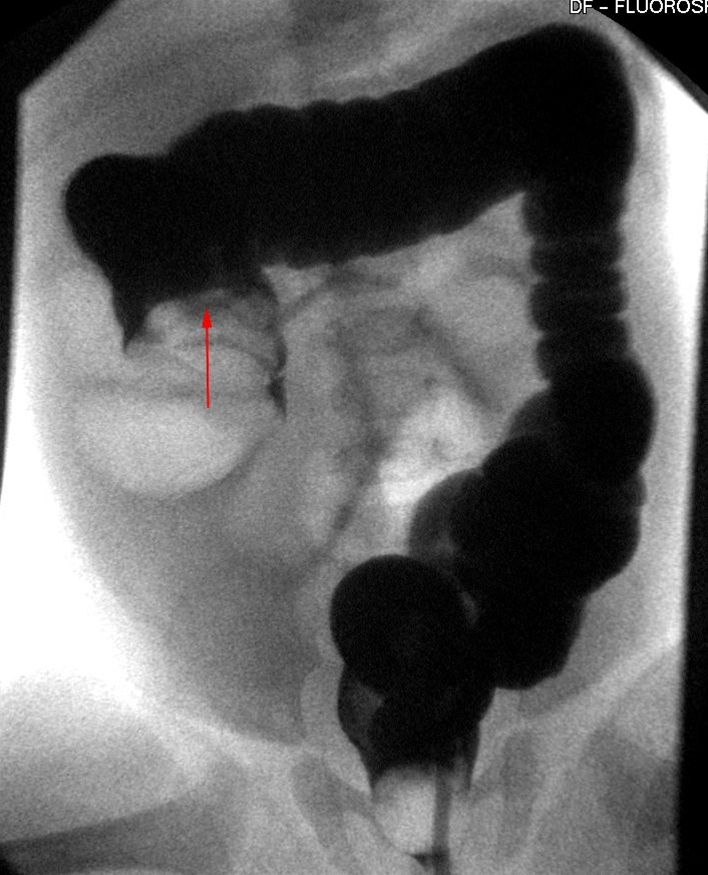

Enkelkontrastundersøgelse af tyktarmen. Terminale ileum og coecum har krænget sig ind i colon ascendens (pil). Ofte kan man ved hjælp af trykket fra colonkontrasten reponere invaginationen. Diagnosen stilles ved hjælp af CT-skanning, og i dag foretages reponeringen oftest med saltvandsindhældning.